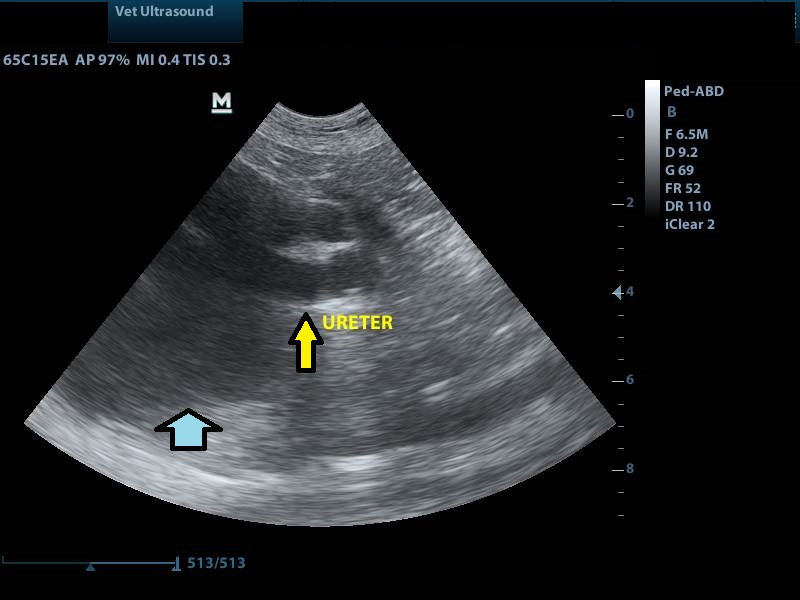

κίτρινο βέλος: έντονη διάταση του ουρητήρα

μπλε βέλος: υδρονέφρωση του αριστερού νεφρού